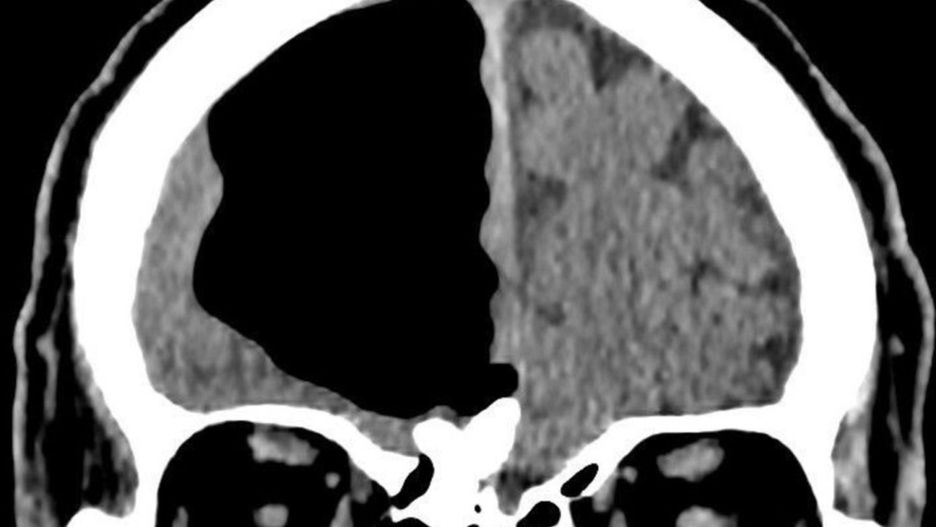

Na zdjęciach najlepiej widać, jak sporej części mózgu brakuje mężczyźnie

Widząc jego wyniki lekarze byli zaszokowani. Okazało się bowiem, że mężczyźnie brakuje sporej części mózgu. Zamiast tkanki mózgowej, lekarze dostrzeli (najprawdopodobniej) pęcherz powietrza o wielkości 9 cm. Na jego miejscu powinna znajdować się duża część prawego płata czołowego. Lekarze ogłosili to odkrycie w BMJ Case Reports.

Jeden z lekarzy, Finlay Brown z Northern Ireland Medical and Dental, przeglądając zdjęcia z prześwietlenie oraz skany tomografii komputerowej określił tę sprawę "kłopotliwą". Zwykle takie pęcherzyki powietrza są widoczne u ludzi, którzy przeszli operację mózgu oraz są zdecydowanie mniejsze. Ale ten mężczyzna nie miał nigdy takiego zabiegu.